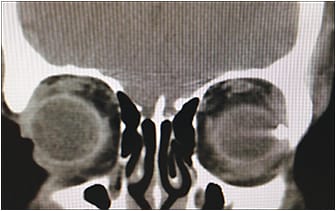

Imaging

Imaging is a very important part of the workup of a patient with an OGI. Computed tomography (CT) scans are fast, widely available, and effective at detecting a wide range of foreign bodies.6 Thin (1-mm) cuts with coronal (Figure 5), axial (Figure 6), and sagittal views are ideal to identify IOFBs and to assess the globe contour, site of posterior rupture, and any other cranial (eg, subarachnoid hemorrhage) or ophthalmic traumatic sequelae (eg, orbital fractures or retrobulbar hemorrhage). Although CT is able to detect most IOFBs well, wood IOFBs are usually hypodense and may be mistaken for air or fat.7 The presence of linear-appearing air should raise suspicion for a wood IOFB. Measuring the Hounsfield units of an IOFB identified on CT may provide some insight into its composition.6